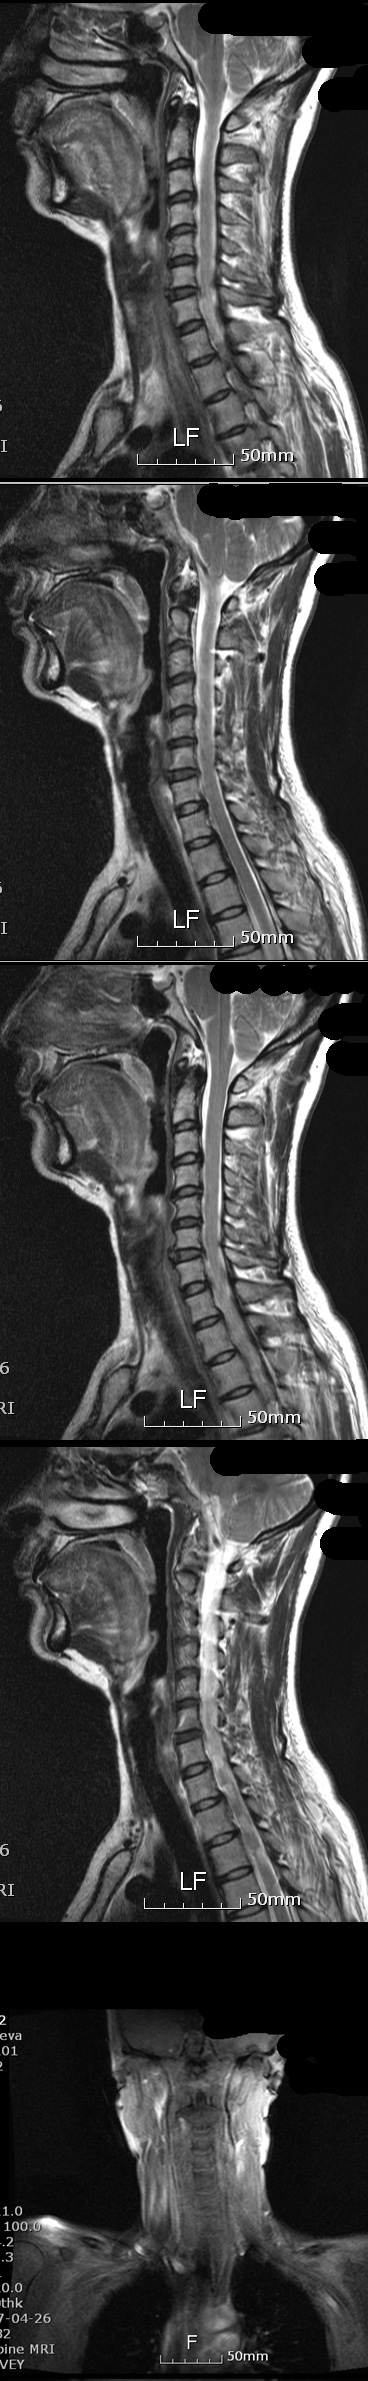

10 ̷ պġ ΰ ȿ 4 ȿ ---------------------- [ֹȣ : 20100709095247team58] ȿ* +ְ 140ȣ ǥغ 10 ̷ պġ ΰ ȿ 4 ȿ 140-190ȣ ο,ûҳ 50~59 Ű 157 Cm ü 51 Kg ۸Ӹ Ű 157 51 54 ˰Ե ͳ ī䳪 α õ ڸǥغ ǥغ ϱ ȣϽ 1C.Ż, 1C.ڵ, 1C.ڵӸ 1C.ٿ, 1C.ٺҸ, 1C.ٰ 1C.ٸǷ 1C.ں 1C.ڱ ֺ 3C.ڱ() 3C.ھ 5C.ھ 6C.ڸ 6C.ھ Ḳ 6C.ڻ 7C.Ȳġ 1T.ڼո 1T.ڼհ ü ̳ 1T.Ȳġ 5T.ڹ߿ 10T.ٸǷ 1L. 5L.ڹ߸̳ 5L.ڹ߰ ̳ ȭŸ̳ ڸǥغ Ը Ͽ , Ḳ ġ Ǵ , , Ǵ ġ Ҹ ġ ߰ ġ Ǵ ġ ڰ, 鹫ȣ, ߵ ڰ Ǵ ġ Ƿ ġ Ǵ ġ ڸǥغ ǥغ ϰ ߴ ġẴ ߺ:10 :1.(). ó - ʾ 㿡 . ٴ÷ ų Ȥ ϱϰ Ǵ õ ̶ . ڰ . 2.- ְ . κ θ κ ó ϰ (Ư Ÿ 鼭 ) 3.- ó 4.Ӹ- Ӹ Ӹ (Ÿ̷ε ) 5.߸- η 6.Ǹ̳ ġẴ:1.**( ȳ) 2.**(MRI,CT-ũ ƴ϶ ) 3.**Ƿ((MRI,-ӻ غڰ..) 4.**뺴(MRI-ũ ƴ϶ ) 5.**뺴(ȣ⳻,Űܰ,ŰŰ: ġ) 6.**ġ(ΰ -ǰߴ ġ9 Ƴ ٽ 7.ü(1ġ)-ä,ô߱,ʻ,ħ.. *纴 ũ ƴ϶մϴ. Ư ** ϳ ܿ ٳϴ. ϴ ϵ 䰡 1 Ǿ.. ͳ ˻ α ũ Ƽ Խϴ. Զ ½ ߿ϴ O ٴϱ 10.. Ե ִϴ. ɷ ο Ǿ ڽϴ. ---------------------- 4 ҰԴϴ. 10 ش , װ ; no 5152 date 2010-07-14 20:52:53 hits 213 name ȿ* (tea***@hanmail.net) IP: 211.200.116.189 10 ش .. װ ;. 㸸 Ǹ ãƿ Ϸ翡 1~2ð ڱġ 10̾. ٸ ΰ (ӹ) ֺ ̸ , ٴ÷ , õ ʹ. δ ûϱ ؼ ִٰ Ա ǵ帮 ҽġ ߴ. ȹٷ ϴ ڼ (ȹٷ ߸ ̻ ٱ ) ڴٺ ô ֹ ;, ̸ ãƿ Ϳ ߸ ڴٰ Ͼ ⸦ 10. ־ Ӹ ο Ǹ ôȴ. ħ Ͼ 뽺 ڿ ¿ ٸ ̻ ٱ ٸ ÷ ݰ ɾҴ. ð ⸦ Ż عٴڿ ݰ ߴ. õİ ˷ ް 鼭 ãƴٴϴ к 5 ܿ ΰ ü ġḦ Ҵ. MRI, CT, ˻縦 Ȯ ߴ. ε ϰ ε ʾ ϴ ϵ ΰ ĥ ģ 쿬 ͳ ˻ ǥغ ˰ Ǿ. ڸ Է ٲ㰡 Ը 17. Ե 3 Ǵٺ ġ μ Ӵ ġ ۿ . Ẹ ϸ ǰ϶ ̾. ȸ絵 ֱ ;. Ը ް 4 ξ ð Ű . Ҿ ִ Ͽ. 1. 1) -ӹ ֺ 2) -, , () 3) Ӹ- Ӹ 4) ΰ 5) 6) Ȳġ ո 7) հ-ڴٰ ǵ帮 ¦ 8) ٸ-ڿ ɾƼ ٸ ̻ ٱ κ (ȹٷ ..) 9) ߸-ȹٷ 10) Ǹ ( 3~4ȸ) 11) ( ó) 12) -ħ Ͼ ǥغ ȸ ǥغ ϱ ȣߴ Ż, , Ӹ, , Ҹ, , Ƿ, ֺ , (), , , , Ḳ , , Ȳġ, ո , հ ü ̳ , ߿, (ε巯) , ߸̳ , ߰ ̳ ȭŸ̳ 2. ġ 1) A-MRI 2) S-MRI, CT( ũ ƴ϶ .) 3) S1-MRI, ˻(ӻ غڰ..) 4) I-ȣ , ̺İ, Ű Ű( ġ) 5) J-MRI( ũ ƴϴ ׳ .) 6) Yġ-ΰ (ǰ ġ 9 Ƴ ٽ , 2) 7) ü -ô , ä, ħ, ʻ(ġ ʹ 뽺) 3. ǥغ ϱ 7/10() :3, Ӹ:3, ħ ħ´ ܿ ̺ 3, е 1 () * ް ´ ȸԲ ȭ ּż ֽ. * ̿ ϰ 2 ð 귶? ó . * ȸԲ ? ִ ̴. * 10 ħ . ̷ !! * ? ȸ ް ħ ̴. * ֿ Ʈ е带 µ κа Ӹ κ ϴ ̴. Ӹ κ Ͽ ̸ ϴ ũ Ӹ ƴ϶ 㸮 ϱ ٸ ϵ Ͽ شٰ Ѵ. Ÿ ִ Ȯ ġ پų Ѵٴ ε Ȯ ġ ϸ Ӹ е带 ְ . Ͻôµ ȸԲ ϴ ŭ е带 ־ 鼭 Ͽ پ Ȯ ־. ̷ 1ð̻ ȭ ٿ űϿ ߸Ǹ ִٰ Ѵ. * Ϸ ִ ٽ (߿ ˰ ǰ ߰ ٽ Ÿ ) * ġ Ȯϰ ġ ȿ ص ʴ´ٴ ǥظƮ û. () * ʴ 㸮 Ǹ . * ϳ ġᰡ ɱ . Ѵ̶ ϰ ڰ ߴ. ٽ ο Ͽ ˰ ٴ ħ ̶. 7/11() :11, Ӹ:2, ħ ǻ ٽ () * 9 ʴ 鼭 ٽ * ̺ ܿ ̺ ٽ Լ * ٽ ٽ * 1ð 2ȸ ( Դٰ ) () * ߴ ٿ (ȿ .) * 5ð ̹ 7/12() :11, Ӹ:2 () * ǥظƮ , 748 * () * 12 ڸ . * 2~210- Դٰ ( 1 3~4ȸ Ͼ ġ) * 210- ɰ ۵Ǵ ܴ ڸ ε巯ó * ߵ, ߸, , Ƹ , , յ, ո, Ȳġ( Ÿ) * ܿ , 㸮, , , Ʒ, . * 4~6ñ ٽ ( ) 7/13(ȭ) :6, Ӹ:6 () * 930а ȸ ٽ (-9 ߿ ־ٰ ) * MRI CD ã * Ϸ ȸԲ ֽ ڼ (պ ) * Ÿ պ 4ð ȿ ڼ. * 330а ٽ * 6~8ñ ( ) () * 11ÿ ʰ ڸ * ʾ 2ð ô̴ ħ 6ñ 7/14() :6 , Ӹ:6 () * 9 45 ȸ ٽ * ణ * , , 㸮 ó ǥغ 4 ǥظƮ 2 ڰ Ͼ 5°. â ۿ Ÿ Ҹ ٽŰ( ħ Ͼ ) å . պ ô!!( ȸԲ ֽ ) ջ ϴ ;ɾҴ ħ Ȱ ־. 10 . Թ翣 ɾ ÿ߸ ä ; Ʒ Ͽ кɾ ư Ͼ ģ ä Ǿ. λ ٽ ϱ? üµ ȸؾ ϰ ǰ ãƾ ϰ ڰ Ͼ ħ. ̰ε ູϰ ູϴ!! ٽ ȸ ǥغԡ в ϸ鼭 ȣ ǰ ı . ֿ ȿ* ø. * : ɴϴ.. ٴ Ѵ 鿩˾ 15.. մϴ..ȭ ^^ 2010-07-14 22:23:31 * : !!! ذ ˴ϴ..ڲٸ þ߰ ϴ.. 2010-07-14 22:39:23 ȿ* : ϴ!! 漮Ե ~~ ȱ!! 2010-07-15 08:13:56 Ȩ : Ͻ *Դϴ. ̵ֹ : 20100709095247team58] Ʈ ù ϼ̽ϴ 2010-07-15 22:28:52 Ȩ : ۼϽ 漮Ե ϼ̰ Ŀ ϴ ִ Դϴ. 2010-07-16 08:19:15 Ȩ : 漮 κ Ӵ ǥظƮ ߰ ϼ̽ϴ. ȸԲ ϼ̰ ° ص帱 Դϴ. 2010-07-16 08:20:44 Ȩ,,,,, : ı մϴ 20100709095247team58] * ֹ ֹϽ 2010-07-16 11:26:38 Ȩ,, : 7094632590816 2010-07-16 16:08:5 * : ذϴ ḸǸ ̷ ״±߽ϴ 1 99%䱹κȭñȿ òϼ 2010-07-20 09:41:49 ȿ* : ϴ! ϴ 2010-07-20 10:25:22 Ȩ : ֽ 漮Ե Ŀ 1 Ѱ ߴ ϸ ֽϴ. ġ ϼ. 2010-07-20 12:15:14 Ȩ : κ ȸ ϼż ȿ Ȯ ȿ Ÿϴ. 輱 迵ռԵ ȸԿ ϸ Ȥ ϴ 찡 ־ ġ µ ð ɸ Ѵϴ. 2010-07-20 12:17:12 * : ..¥..ϳ.. ̷ ߿ ... .. ʱ.. ̿ ˰ Ǿ..ʹ ູؿ~! ƺ ҸӴ .. 2010-07-23 10:17:46 ȿ* : ! ٰ ִ ϴ. ֺ ݽŹϰ ִ .. Բ ̴ٴ ϵ帳ϴ!! 2010-07-23 11:09:21 -------------------------------------------------------------------------------------------------------------------------------------------- ٰ ִ ϱ? no 5180 date 2010-07-17 13:11:58 hits 187 name ȿ* (team**@hanmail.net) IP: 211.200.116.189 ǥغ 귶. â ۿ ߰ ̸ Ϸ .. ۾˼۾ ִ ٶ 10 Ǹ Ҵ ð ҷ. Ͼ ϱ? ٰ ִ ϱ? ʴ. ϴ ̷ ɾ ٳణ ̹ ó Ӵ. ջ꿣 ܿ ҳ ø ä ° ְ ߷ ͱ ö ٱ Ǫ ʿŸ. ñ ̿ г . ΰ ȭӰ ΰ ູϰ ΰ Ӵ. 28 ڸ Ƹ Ǫ ̴.(ȥ) ̷ ä ð, ؾ߰ڴ. ʰ ູ Ǫ Ű Ű ڳ.. Կ װ ִ ٶ ڸ ı鿡 Ѵ. ϴ! ϴ! մϴ! ֿ ȿ* ø * : Ʒ..幮 ̴ּ ̽ñ~ ...ۼؾ Ͻó.. 뿡 ̴ٴ.. .. .. ʿ䰡 ° ƿ..ȣ~ ູؿ~ 2010-07-23 10:19:26 ȿ* : Բ ּż ϴ! Ϸ ٱ Ϸ ٻµ ´ϴ. ٸ ڼ ϸ鼭 Ͽ Ѵٴ ȸ ʰ ÷ ϰ ֽϴ. 忡 2010-07-23 11:16:20 ȿ* : Բ ּż ϴ! Ϸ ٱ Ϸ ٻµ ´ϴ. ٸ ڼ ϸ鼭 Ͽ Ѵٴ ȸ ʰ ÷ ϰ ֽϴ. 忡 2010-07-23 11:16:20 ȿ* : ٰ, ĿǼ, .. ʾ ~~ 2010-07-23 11:20:43 |